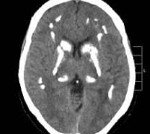

Основным диагностическим методом, позволяющим неврологу достоверно установить наличие очагов кальциноза в мозговых тканях, является КТ головного мозга. Интенсивность очагов на томограммах отражает уровень концентрации кальция. МРТ головного мозга значительно хуже визуализирует кальцификаты, но позволяет оценить сопутствующие дегенеративные процессы. С целью подтверждения идиопатического характера патологии проводится целый ряд дополнительных обследований:

Болезнь Фара. Идиопатическая симметричная кальцификация церебральных структур - подкорковых ганглиев, коры полушарий, мозжечка. Может протекать бессимптомно, клинически проявляется экстрапирамидными расстройствами (гиперкинезами, паркинсонизмом), мозжечковыми нарушениями, интеллектуальным снижением. Диагностируется по данным церебральной КТ при исключении вторичного характера кальцинированных очагов по результатам биохимических, ультразвуковых, ПЦР исследований. Лечение симптоматическое с применением средств, улучшающих тканевый обмен, цитопротекторов, препаратов леводопы, антиконвульсантов.